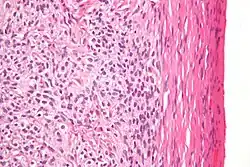

| High magnification micrograph of a thecoma. H&E stain. | |

Microscopically, the tumour cells have abundant lipid-filled cytoplasm.